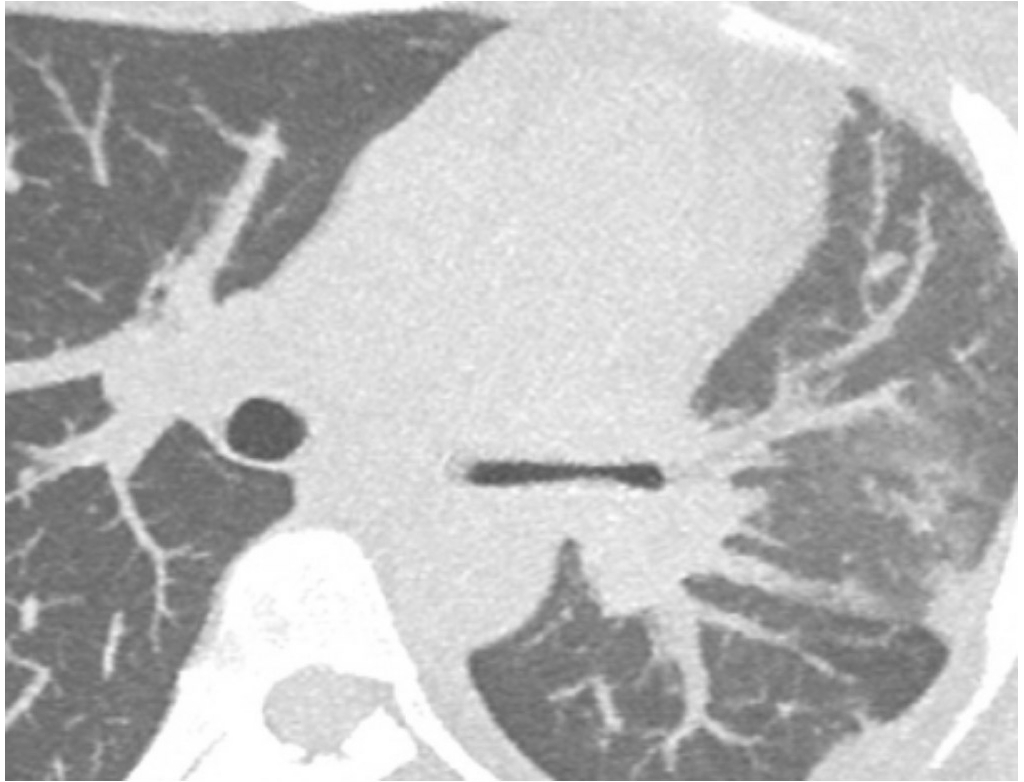

A 37-year-old G1P1 female with known idiopathic FM and a previous mediastinectomy presented at 23 weeks and 3 days with preterm labor and cervical dilation to 4 cm. She received steroids and magnesium for fetal neuroprotection. In the days prior to delivery, she experienced hemoptysis, prompting pulmonology consultation. She was managed conservatively with chest physiotherapy and nebulizers. The patient had no more hemoptysis and at 24 weeks and 1 day, she underwent classical cesarean delivery for breech presentation and non-reassuring fetal heart tones. The neonate was admitted to NICU and the patient was discharged in stable condition. Outpatient imaging revealed a stable calcified mediastinal mass causing 80% narrowing of the left main bronchus and left lung atelectasis. Subsequent bronchoscopy with balloon dilation improved airway patency, but stenting was deferred.

FM can remain stable during pregnancy, but physiologic changes in pregnancy such as increases in blood volume and cardiac output can be exacerbated by FM, potentially leading to pulmonary hypertension and reduced blood flow to the uterus. Notably, FM-related airway obstruction may not always present with overt respiratory distress and can be managed conservatively in select patients. Also, while balloon dilation may offer symptomatic relief, stenting decisions must be individualized based on functional status and patient preference. Finally, early multidisciplinary collaboration is crucial to prepare for peripartum respiratory complications in patients with known mediastinal pathology.